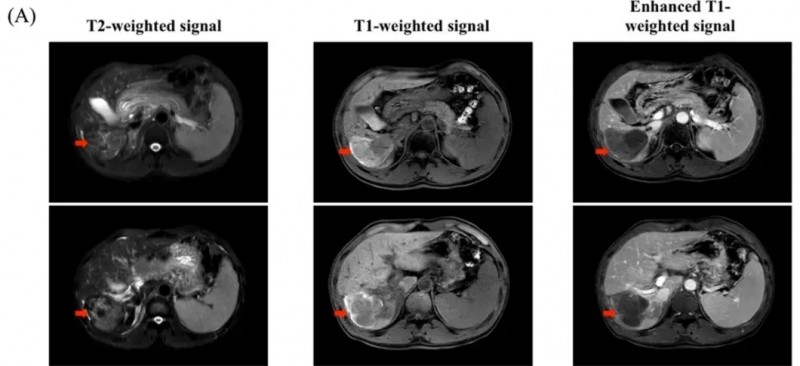

结果显示:中位观察12个月时,完全缓解(CR)率达85.7%(7/8),5例获持久缓解,1例获部分缓解(PR),最佳客观缓解率(ORR)达100%;且未发生严重不良事件,充分印证其安全性与有效性。下图展示了三例代表性患者治疗前后的PET-CT扫描,红色箭头表示肿瘤病变(详见下图)。

▲图源“nature”,版权归原作者所有,如无意中侵犯了知识产权,请联系我们删除